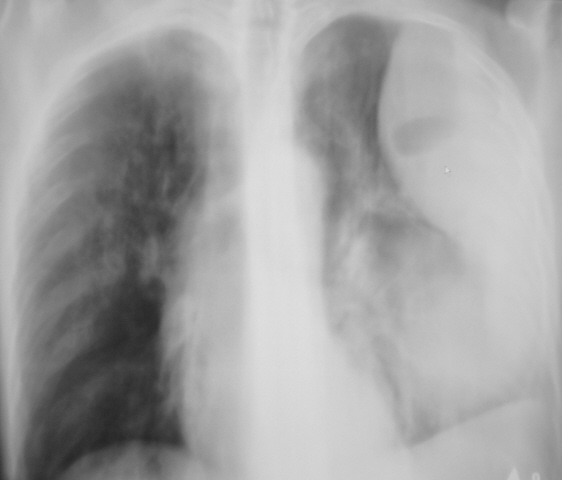

Иллюстрация 2. Слева определяется субтотальное снижение прозрачности легочного поля за счет наличия значительных размеров паракостального осумкованного выпота, имеющего чёткий и ровный контур. На фоне инфильтративно измененной легочной ткани в верхнем, среднем и нижнем легочных полях четко определяются две структуры — просветления с горизонтальными уровнями жидкости. Слева купол диафрагмы подтянут, фиксирован. Тень средостения резко смещена вправо.